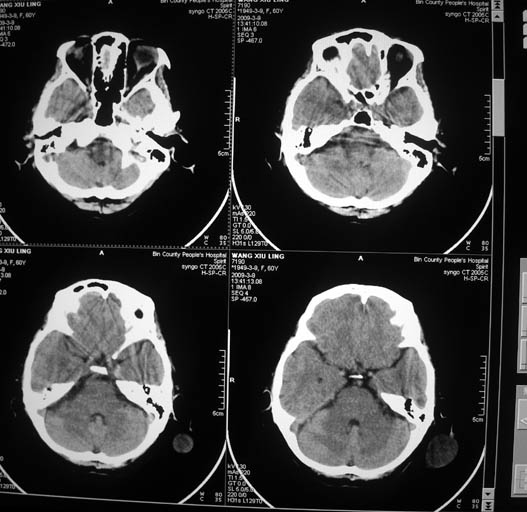

标题: CT18574:女,60岁,头部肿物。 [打印本页]

标题: CT18574:女,60岁,头部肿物。

女,60岁,头部肿物。ct值为12hu。